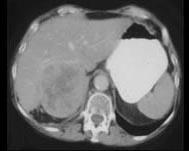

问题 女,37岁,向心性肥胖2个月,请结合所提供图像,作出诊断 ( )

选项 A、右肾上腺嗜铬细胞瘤 B、右肾上腺增生 C、右肾上腺腺癌 D、右肾上腺转移瘤 E、右肾上腺腺瘤

答案 C